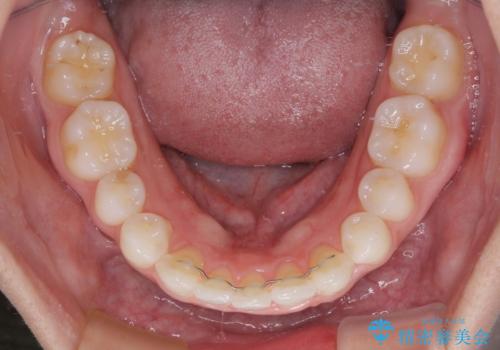

- 前歯の歯並びと神経を取って変色してしまった前歯を気にして来院された患者様です。

上下前歯の歯列不正はインビザラインにより整え、その後に、前歯2本をオールセラミッククラウンにて補綴治療することとしました。

下顎前歯が1本欠損しており、下顎歯列の大きさが本来よりも小さいため、上顎歯列とのバランスが悪く、深い咬み合わせになっていました。

上顎にIPRを多用して歯列の大きさを小さくするよう試みましたが、理想的な咬み合わせまでには改善させることはできませんでした。